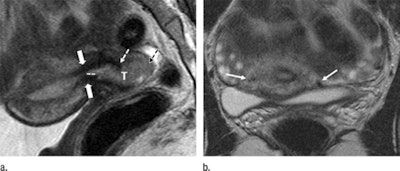

MR images show the tumor-to-internal-os distance and presence of deep cervical stromal invasion in a 23-year-old woman with stage IB1 invasive adenocarcinoma of the uterine cervix. Sagittal (left) and axial (right) images show a tumor (T) within 3 mm of the internal os. Images courtesy of Radiology.For tumors smaller than 20 mm, the mean differences between tumor sizes based on pathology results and MRI were 0.1 mm for the first reader and 1.7 mm for the second reader. For tumors 20 mm or larger, the mean differences were 2.0 mm for the first reader and 3.5 mm for the second reader. Combining their results, eight patients (80%) with tumors 20 mm or larger on MR images received radical hysterectomy.